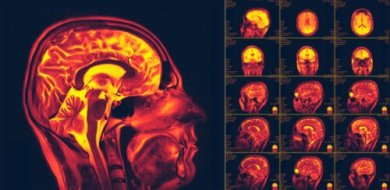

A neuroplasticidade, também chamada de plasticidade cerebral, é uma das descobertas mais importantes sobre o corpo humano nas últimas décadas. Consiste na capacidade do nosso cérebro de mudar e se adaptar em resposta a novos comportamentos ou experiências.

A neuroplasticidade é a capacidade de nossos neurônios se regenerarem, tanto anatomicamente quanto funcionalmente. É um processo que envolve muitas reações bioquímicas e metabólicas, mas que implica um grande potencial de adaptação.

Começou-se então a realizar diferentes exames de imagem e estimulação com os quais foi possível demonstrar a existência de neuroplasticidade. Atualmente, todos os mecanismos envolvidos nesse processo ainda estão sendo investigados.